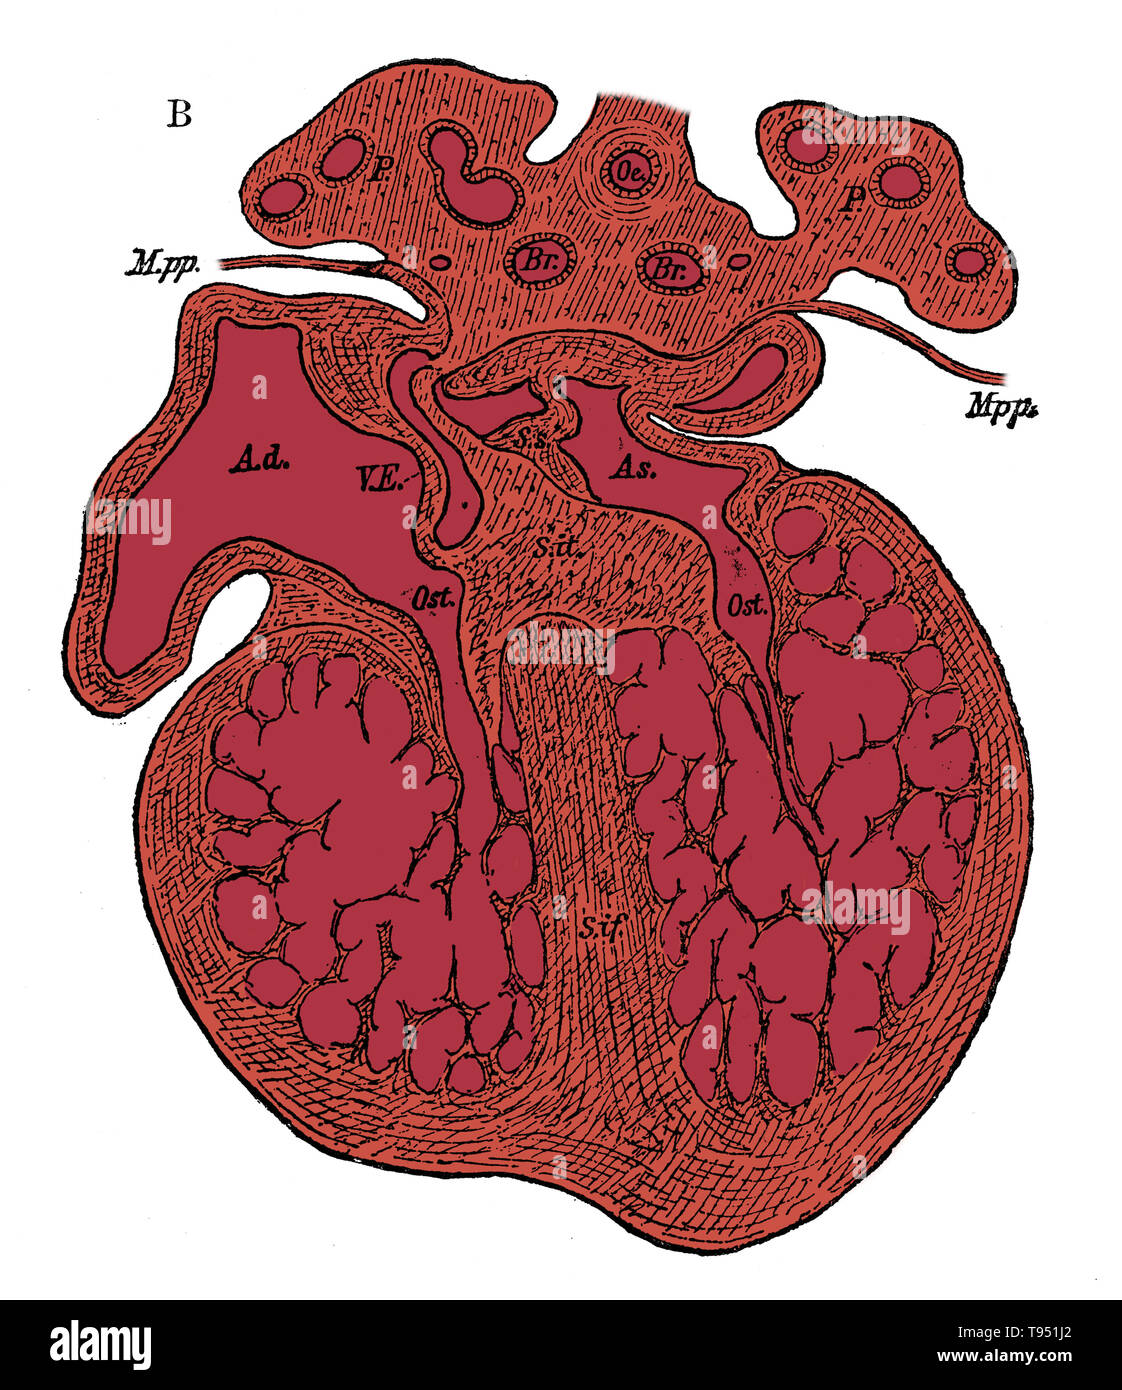

Section through the heart of human embryo showing the formation of the cardiac septa and the auriculo-ventricular valves, (see 9N3690) from a somewhat more advanced embryo. Ad, As, right and left auricle; Ost, auriculo-ventricular apertures; S.s, septum superior of auricles; S. it, endocardial cushion (septum intermedium); S. if, septum infers ventriculorum, now denser and more muscular. Stock Photohttps://www.alamy.com/image-license-details/?v=1https://www.alamy.com/section-through-the-heart-of-human-embryo-showing-the-formation-of-the-cardiac-septa-and-the-auriculo-ventricular-valves-see-9n3690-from-a-somewhat-more-advanced-embryo-ad-as-right-and-left-auricle-ost-auriculo-ventricular-apertures-ss-septum-superior-of-auricles-s-it-endocardial-cushion-septum-intermedium-s-if-septum-infers-ventriculorum-now-denser-and-more-muscular-image246588106.html

Section through the heart of human embryo showing the formation of the cardiac septa and the auriculo-ventricular valves, (see 9N3690) from a somewhat more advanced embryo. Ad, As, right and left auricle; Ost, auriculo-ventricular apertures; S.s, septum superior of auricles; S. it, endocardial cushion (septum intermedium); S. if, septum infers ventriculorum, now denser and more muscular. Stock Photohttps://www.alamy.com/image-license-details/?v=1https://www.alamy.com/section-through-the-heart-of-human-embryo-showing-the-formation-of-the-cardiac-septa-and-the-auriculo-ventricular-valves-see-9n3690-from-a-somewhat-more-advanced-embryo-ad-as-right-and-left-auricle-ost-auriculo-ventricular-apertures-ss-septum-superior-of-auricles-s-it-endocardial-cushion-septum-intermedium-s-if-septum-infers-ventriculorum-now-denser-and-more-muscular-image246588106.htmlRMT951J2–Section through the heart of human embryo showing the formation of the cardiac septa and the auriculo-ventricular valves, (see 9N3690) from a somewhat more advanced embryo. Ad, As, right and left auricle; Ost, auriculo-ventricular apertures; S.s, septum superior of auricles; S. it, endocardial cushion (septum intermedium); S. if, septum infers ventriculorum, now denser and more muscular.